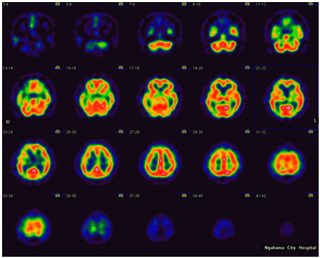

核医学装置

脳血流SPECT